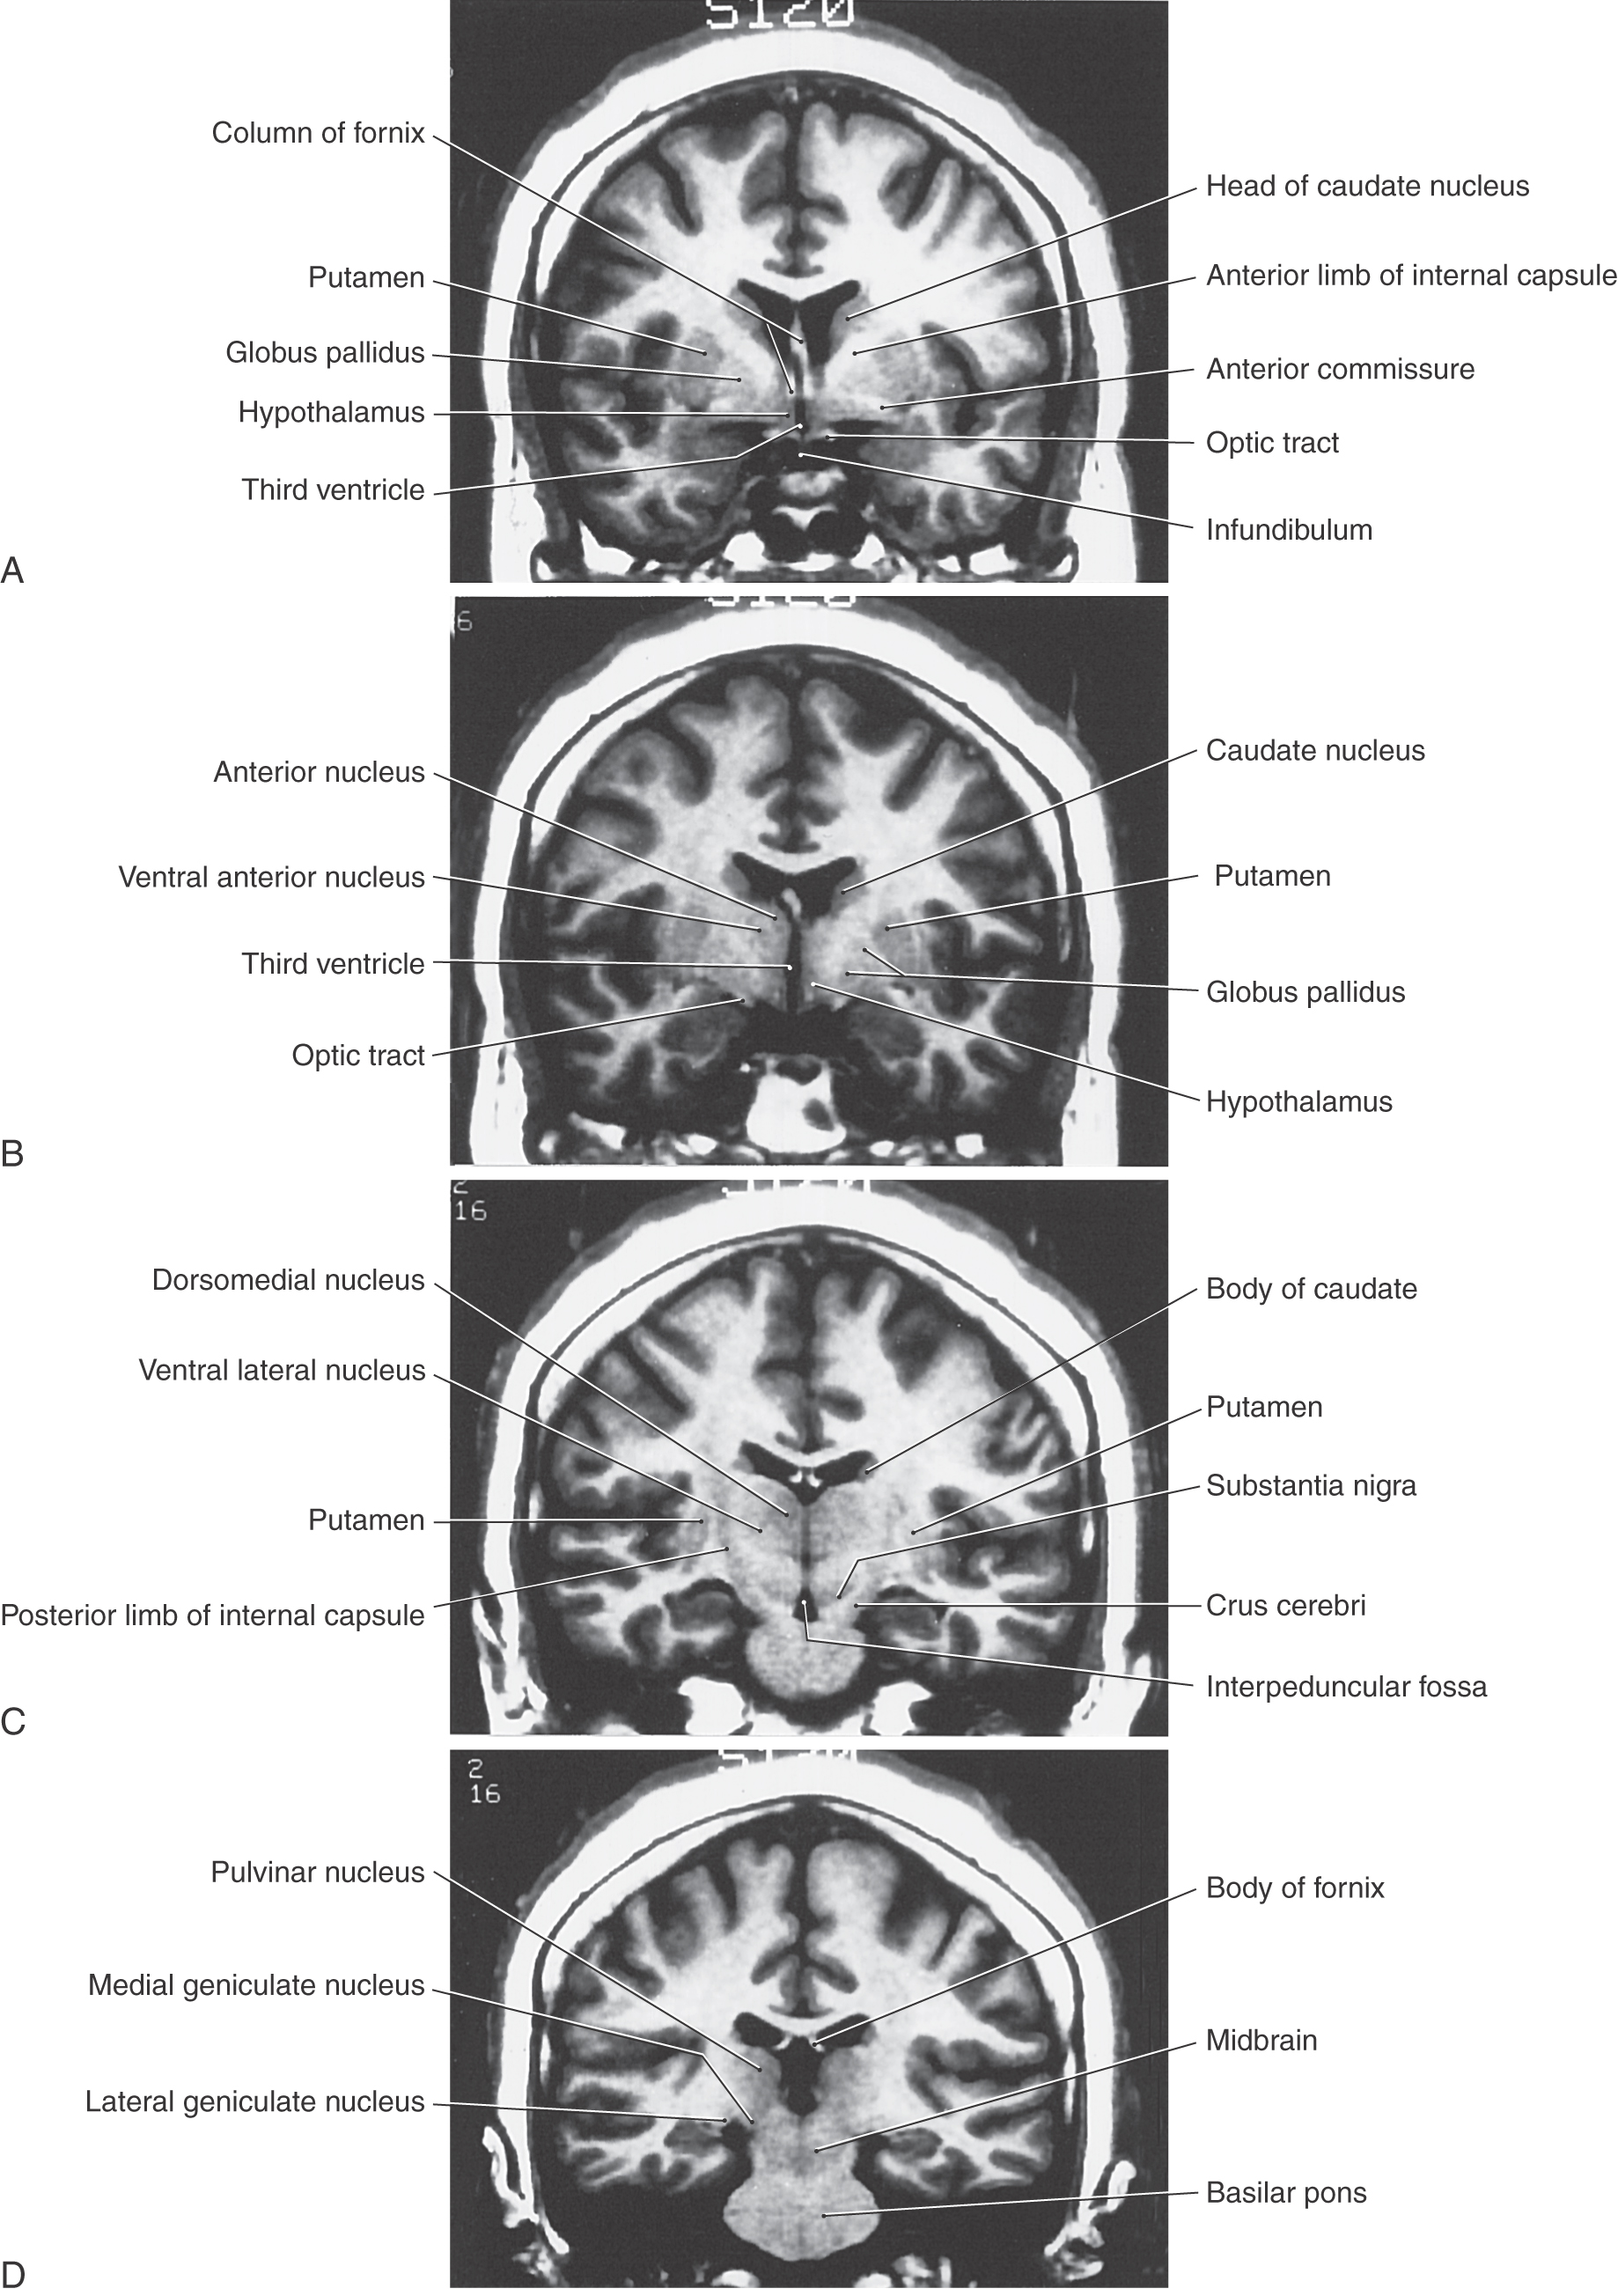

image

Figure 15-8. Magnetic resonance images of the cerebral hemisphere in the coronal plane from rostral (A) to caudal (D). Although many structures are clearly seen, emphasis in the labeling is placed on diencephalic structures. All images are T1 weighted.